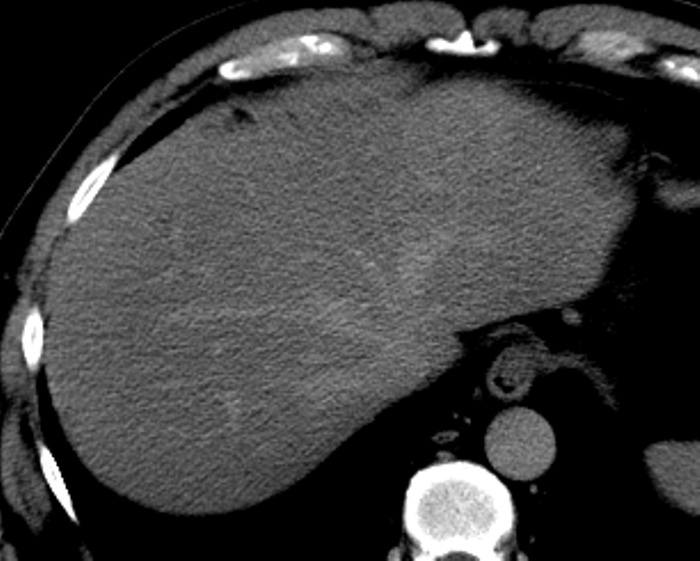

Ung thư đường mật

» Thông tin: Nam giới – 57 tuổi.

» Lâm sàng: Đau bụng.